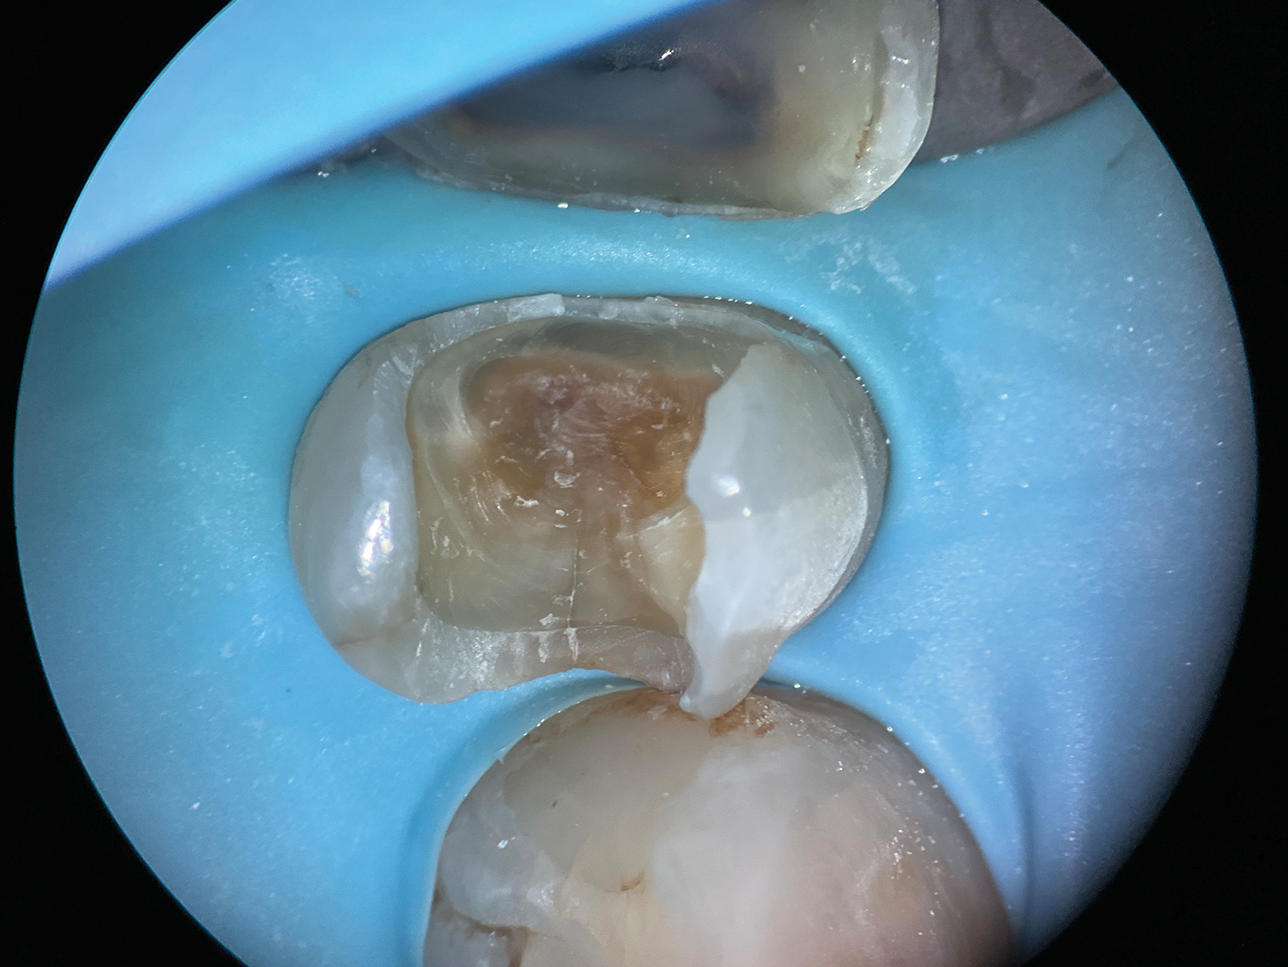

(2.) Close-up occlusal view of a maxillary first premolar during restorative treatment revealing a mesial structural crack.

Figure 2

(3.) Close-up occlusal view of the maxillary first premolar after removal of the thin cusps and dissection of the mesial crack, which resulted in a subgingival margin.

Figure 3

(5.) Close-up occlusal view of the modified copper band placed to isolate the margin during deep margin elevation and stabilized with a wedge and a piece of polytetrafluoroethylene tape.

Figure 5

(6.) Absolute adaptation and isolation was achieved with the copper band, conforming to the unique anatomy of the upper premolar.

Figure 6